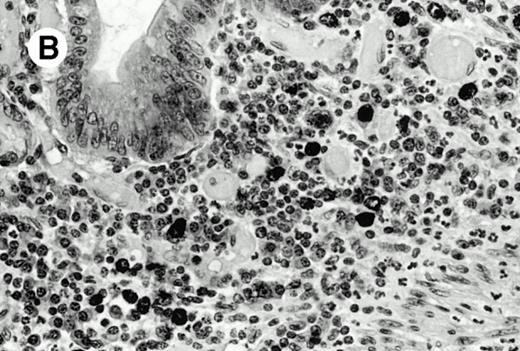

All cases were studied for cytotoxic markers. All of them demonstrated a strong granular cytoplasmic positivity for the cytotoxic granule-associated protein TIA-1. A variable proportion of neoplastic cells were also found positive with Granzyme B (Fig 4A and B) in all cases. Staining for perforin was performed on frozen sections in nine cases, of which seven were positive, one was negative, and the remaining was not interpretable.

Granzyme B expression. (A) Strong paranuclear staining of neoplastic cells in a nasal lymphoma (case no. 3); (B) strong cytoplasmic staining of a few neoplastic cells surrounding intestinal glands in an enteropathy-associated γδ T-cell lymphoma (case no. 11). (Paraffin-embedded section, APAAP technique.)